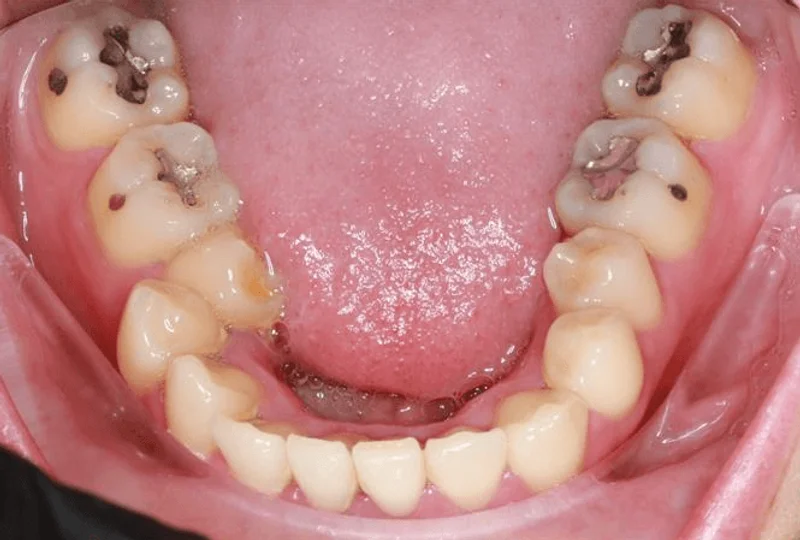

Lower Occlusal

Lower Occlusal - Before Treatment

Before